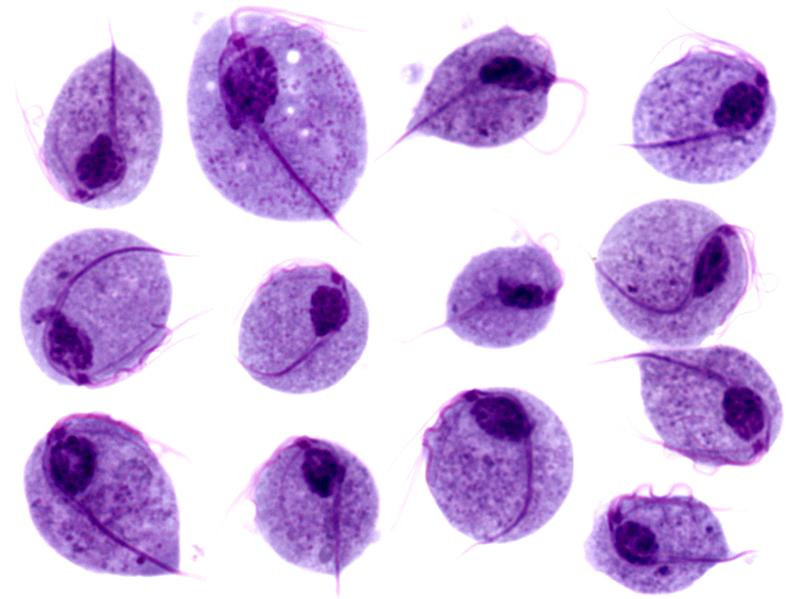

Bij Trichomonas ziet men een milde balanitis met erosies met speldepunt grote grijzige vesikeltjes op erythemateuze ondergrond, soms ulceraties.

Trichomonas vaginalis, trichomoniasis Trichomonas vaginalis, trichomoniasis

Trichomonas vaginalis Trichomonas vaginalis

Foto's Trichomonas: isis325 en fickleandfreckled - Wikimedia (Creative Commons License 2.0).

Onderzoek: direct preparaat van de laesies.